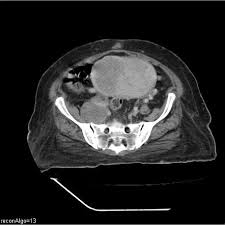

Get Stage 4 Bladder Cancer Ct Scan Pictures. For bladder cancer, the stage is determined based on examining the sample removed during a turbt (see diagnosis) and finding out whether the clinical staging is based on the results of tests done before surgery, which may include history, physical examinations, imaging scans, and biopsies. Like ct scans, mri scans show detailed images of soft tissues in the body.

Patients who have been diagnosed with stage iv cancer may consider getting a second opinion to confirm the diagnosis and explore treatment options. It may also have spread to lymph nodes and distant sites in the body. You may be offered a ct scan or an mri scan if the specialist feels they need a more detailed picture of your bladder.

Therefore computer aided diagnosis can be helpful for doctors to identify the cancerous keyword: See all parts of this guide hide guide parts. A ct scan provides a the outlook for bladder cancer patients depends on the stage of cancer at the time of diagnosis. Bladder cancer begins when cells in the urinary bladder start to grow uncontrollably.